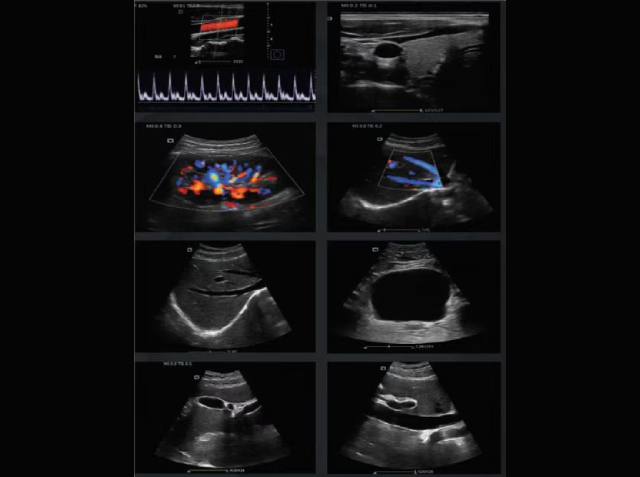

Taking a patient who had coronary artery bypass grafting and prosthetic mitral valve replacement five days later as an example, it can be clearly seen that the patient's mitral valve opens and closes freely, and the cardiac contraction is enhanced. The image below is an ultrasound image in color Doppler mode.